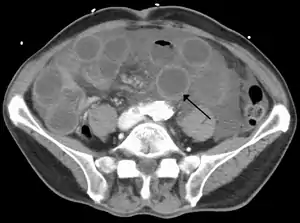

Computed tomography (CT) showing dilated loops of small bowel with thickened walls (black arrow), findings characteristic of ischemic bowel due to thrombosis of the superior mesenteric vein.

Computed tomography (CT scan) is often used.[29][30] The accuracy of the CT scan depends on whether a small bowel obstruction (SBO) is present.[31]

Early findings on CT scan include:

• Mesenteric edema[29]

• Bowel dilatation[29]

• Bowel wall thickening[29]

• Mesenteric stranding[32]